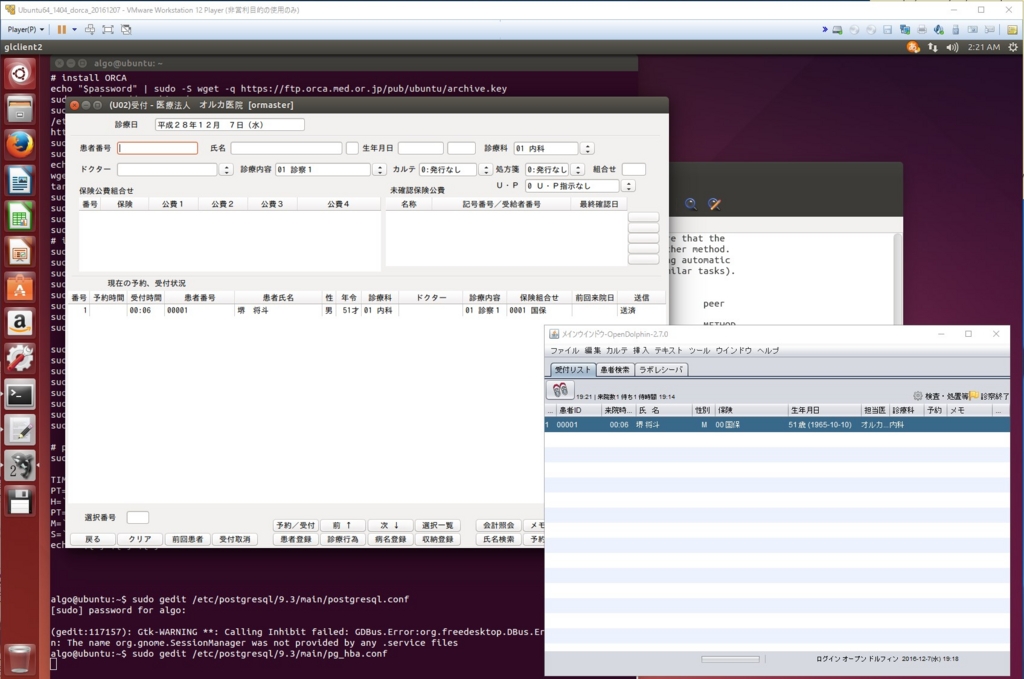

以前ブログで、OpenDolphin(電子カルテ)とORCA(日医レセコン)の環境構築について書いたところ、OpenDolphinデータベースを二次利用できるのかコメントをいただきました。

実際OpenDolphinで電子カルテを運用されている方の参考にもなるかもしれないので、仮想マシンでの環境構築とRstudioでの接続までを書いておきます。

いつも通りUbuntu仮想マシン(Ubuntu1404)を用意します。

インストール用のスクリプトは上記ブログ内のものとほぼ同じですが、OpenDolphinのDockerコンテナで使用しているPostgreSQLと、ORCAのPostgreSQLのポートがぶつからないように、Docker runするときにPort(5433)を指定しています(通常は5432)。RstudioもクライアントPCにインストールするのが面倒なので、Dockerコンテナで入れちゃいます。

あとは、シェルスクリプトを実行するだけです。

$ sh dorca.sh

うちの通信環境とPCスペックだと、シェルスクリプトの実行時間は35分程度です。

途中ORCAの設定等の入力を求められますが、上記サイトに書いてある通り入力してください。

では今回のポイントのOpenDolphinとRstudioの接続です。

ORCAから患者登録をして、OpenDolphinでカルテに書き込んで、Rstudioで実際にデータベースを確認してみると、いろいろアイデアが浮かんでくるかと思います。

OpenDolphinとORCAの簡単な環境構築

OpenDolphinは日医レセコンORCAに接続できる、オープンソースの電子カルテです。

極力インストールの手間を省略するためと、ホストOSの環境をよごさないために、VMwareの仮想マシンにUbuntu64,14.04LTSをインストールし、そこにORCAをインストールします。またOpenDolphinはUbuntuのDockerを利用してインストールします。

Ubuntuが苦手、Dockerがわからなくても環境構築できるように、シェルスクリプトを使ってコード入力を少なくすることにします。

つぎつぎスクリプトが実行されていきます。前半はORCAのインストール、後半はDockerのインストールとOpenDolphinに必要なDockerImageのダウンロード、コンテナの実行です。とりあえずここではDockerとかコンテナとかわからなくて問題ありません。

途中で確認入力を要求されたらy[yes]と入れてください。

後半でORCAのデータベースPostgresの設定画面が開きます。

59行目、listen_addressesの前の'#'をはずし、仮想化ソフトを動かしているOS(僕はWindows10)のアドレスを追加します。

保存して終了します。次に別の設定ファイルが起動します。

最終行に'host all all 0.0.0.0/0 trust'を追加して、保存して終了します。

CLAIMサーバーの設定は、No、No、の次が下の画面になるのでYes、

Portはそのまま

最後にORCAのパスワードを確認されますので8桁以上のパスワードを入力しましょう。

これでサーバーの準備は完了です。